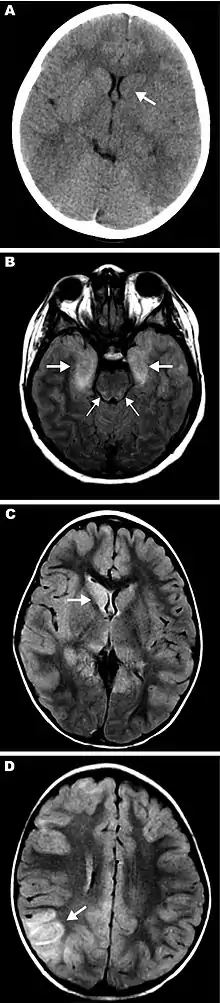

Eastern equine encephalitis (EEE), commonly called Triple E or sleeping sickness (not to be confused with African trypanosomiasis), is a disease caused by a zoonotic mosquito vectored Togavirus that is present in North, Central, and South America, and the Caribbean. EEE was first recognized in Massachusetts, United States, in 1831, when 75 horses died mysteriously of viral encephalitis. Epizootics in horses have continued to occur regularly in the United States. It can also be identified in donkeys and zebras. Due to the rarity of the disease, its occurrence can cause economic impact beyond the cost of horses and poultry.[2] EEE is found today in the eastern part of the United States and is often associated with coastal plains. It can most commonly be found in East Coast and Gulf Coast states.[1] In Florida, about one to two human cases are reported a year, although over 60 cases of equine encephalitis are reported. In years in which conditions are favorable for the disease, the number of equine cases is over 200.[3] Diagnosing equine encephalitis is challenging because many of the symptoms are shared with other illnesses and patients can be asymptomatic. Confirmations may require a sample of cerebral spinal fluid or brain tissue, although CT scans and MRI scans are used to detect encephalitis. This could be an indication that the need to test for EEE is necessary. If a biopsy of the cerebral spinal fluid is taken, it is sent to a specialized laboratory for testing.[4]

- Deresiewicz RL, Thaler SJ, Hsu L, Zamani AA (1997). "Clinical and neuroradiographic manifestations of eastern equine encephalitis". N. Engl. J. Med. 336 (26): 1867–74. doi:10.1056/NEJM199706263362604. PMID 9197215.